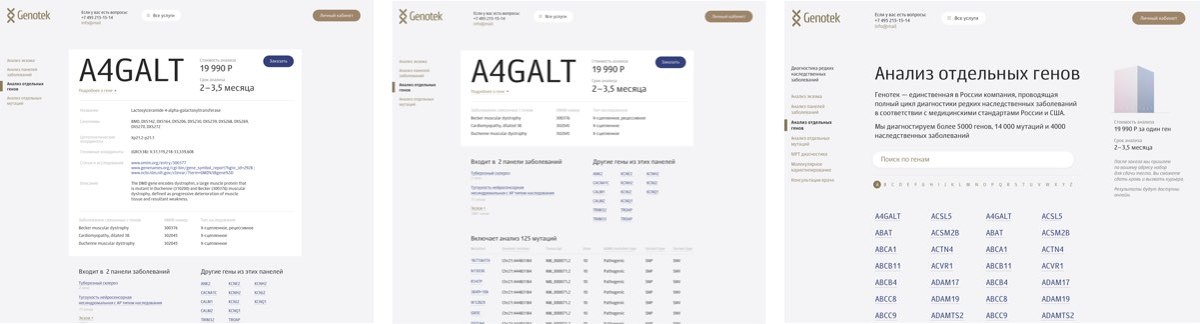

Working on diagnostic tests. Their pages have to contain maximum information since they will be used by doctors and their patients. Not a place for entertainment.

Coming up with the first draft of gene pages.

Getting the client feedback and starting to work on the panels for disorders and mutations. Sketching the appearance of diagnostic test pages.